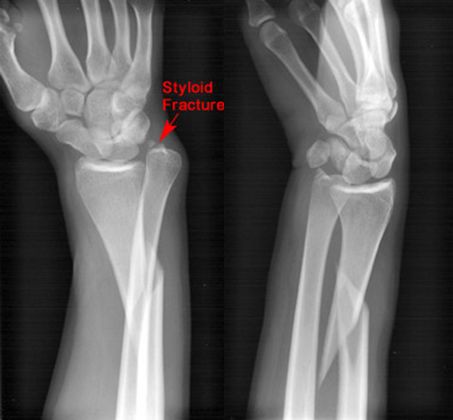

Colles骨折

桡骨远端骨折

骨折向掌侧成角

远折端向背侧移位

Smith骨折